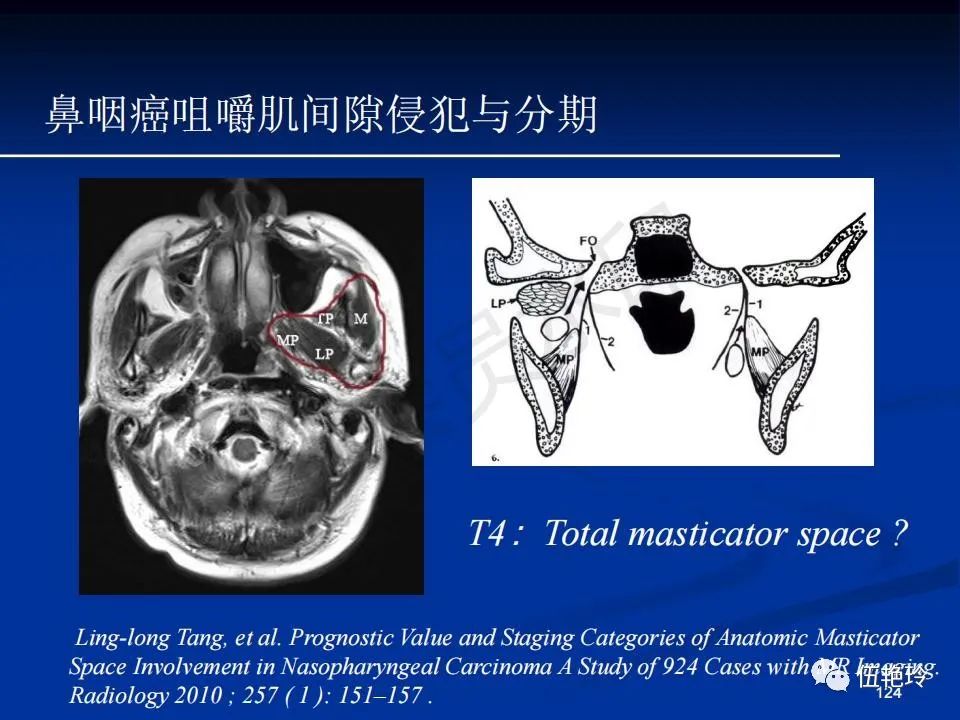

颞下窝与咀嚼肌间隙